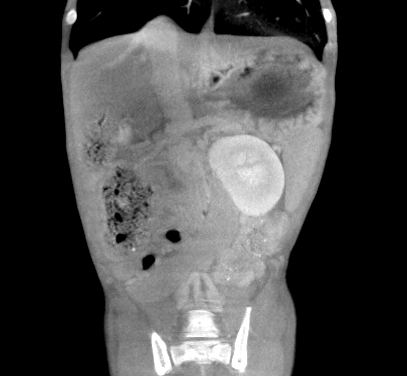

CT検査

シャント血管の発見にはCT検査が一番有効だと考えられます。血管の走行を立体的に把握し、問題点を明確に描出することが可能です。特に血管造影という方法を用いて、血液の流れを確認することで確定的な診断につながります。

門脈体循環シャントの分類について

シャント血管はおおよそ分類がされており、ある程度、その形などが決まっています。

などがその代表としてあげられます。診断のうえで、分類分けをしておくことは、手術をする際の重要な指標となりますので、必ず意識しておく必要があります。また、分類によって、症状が強くでるものや、あまり症状のないものがあります。